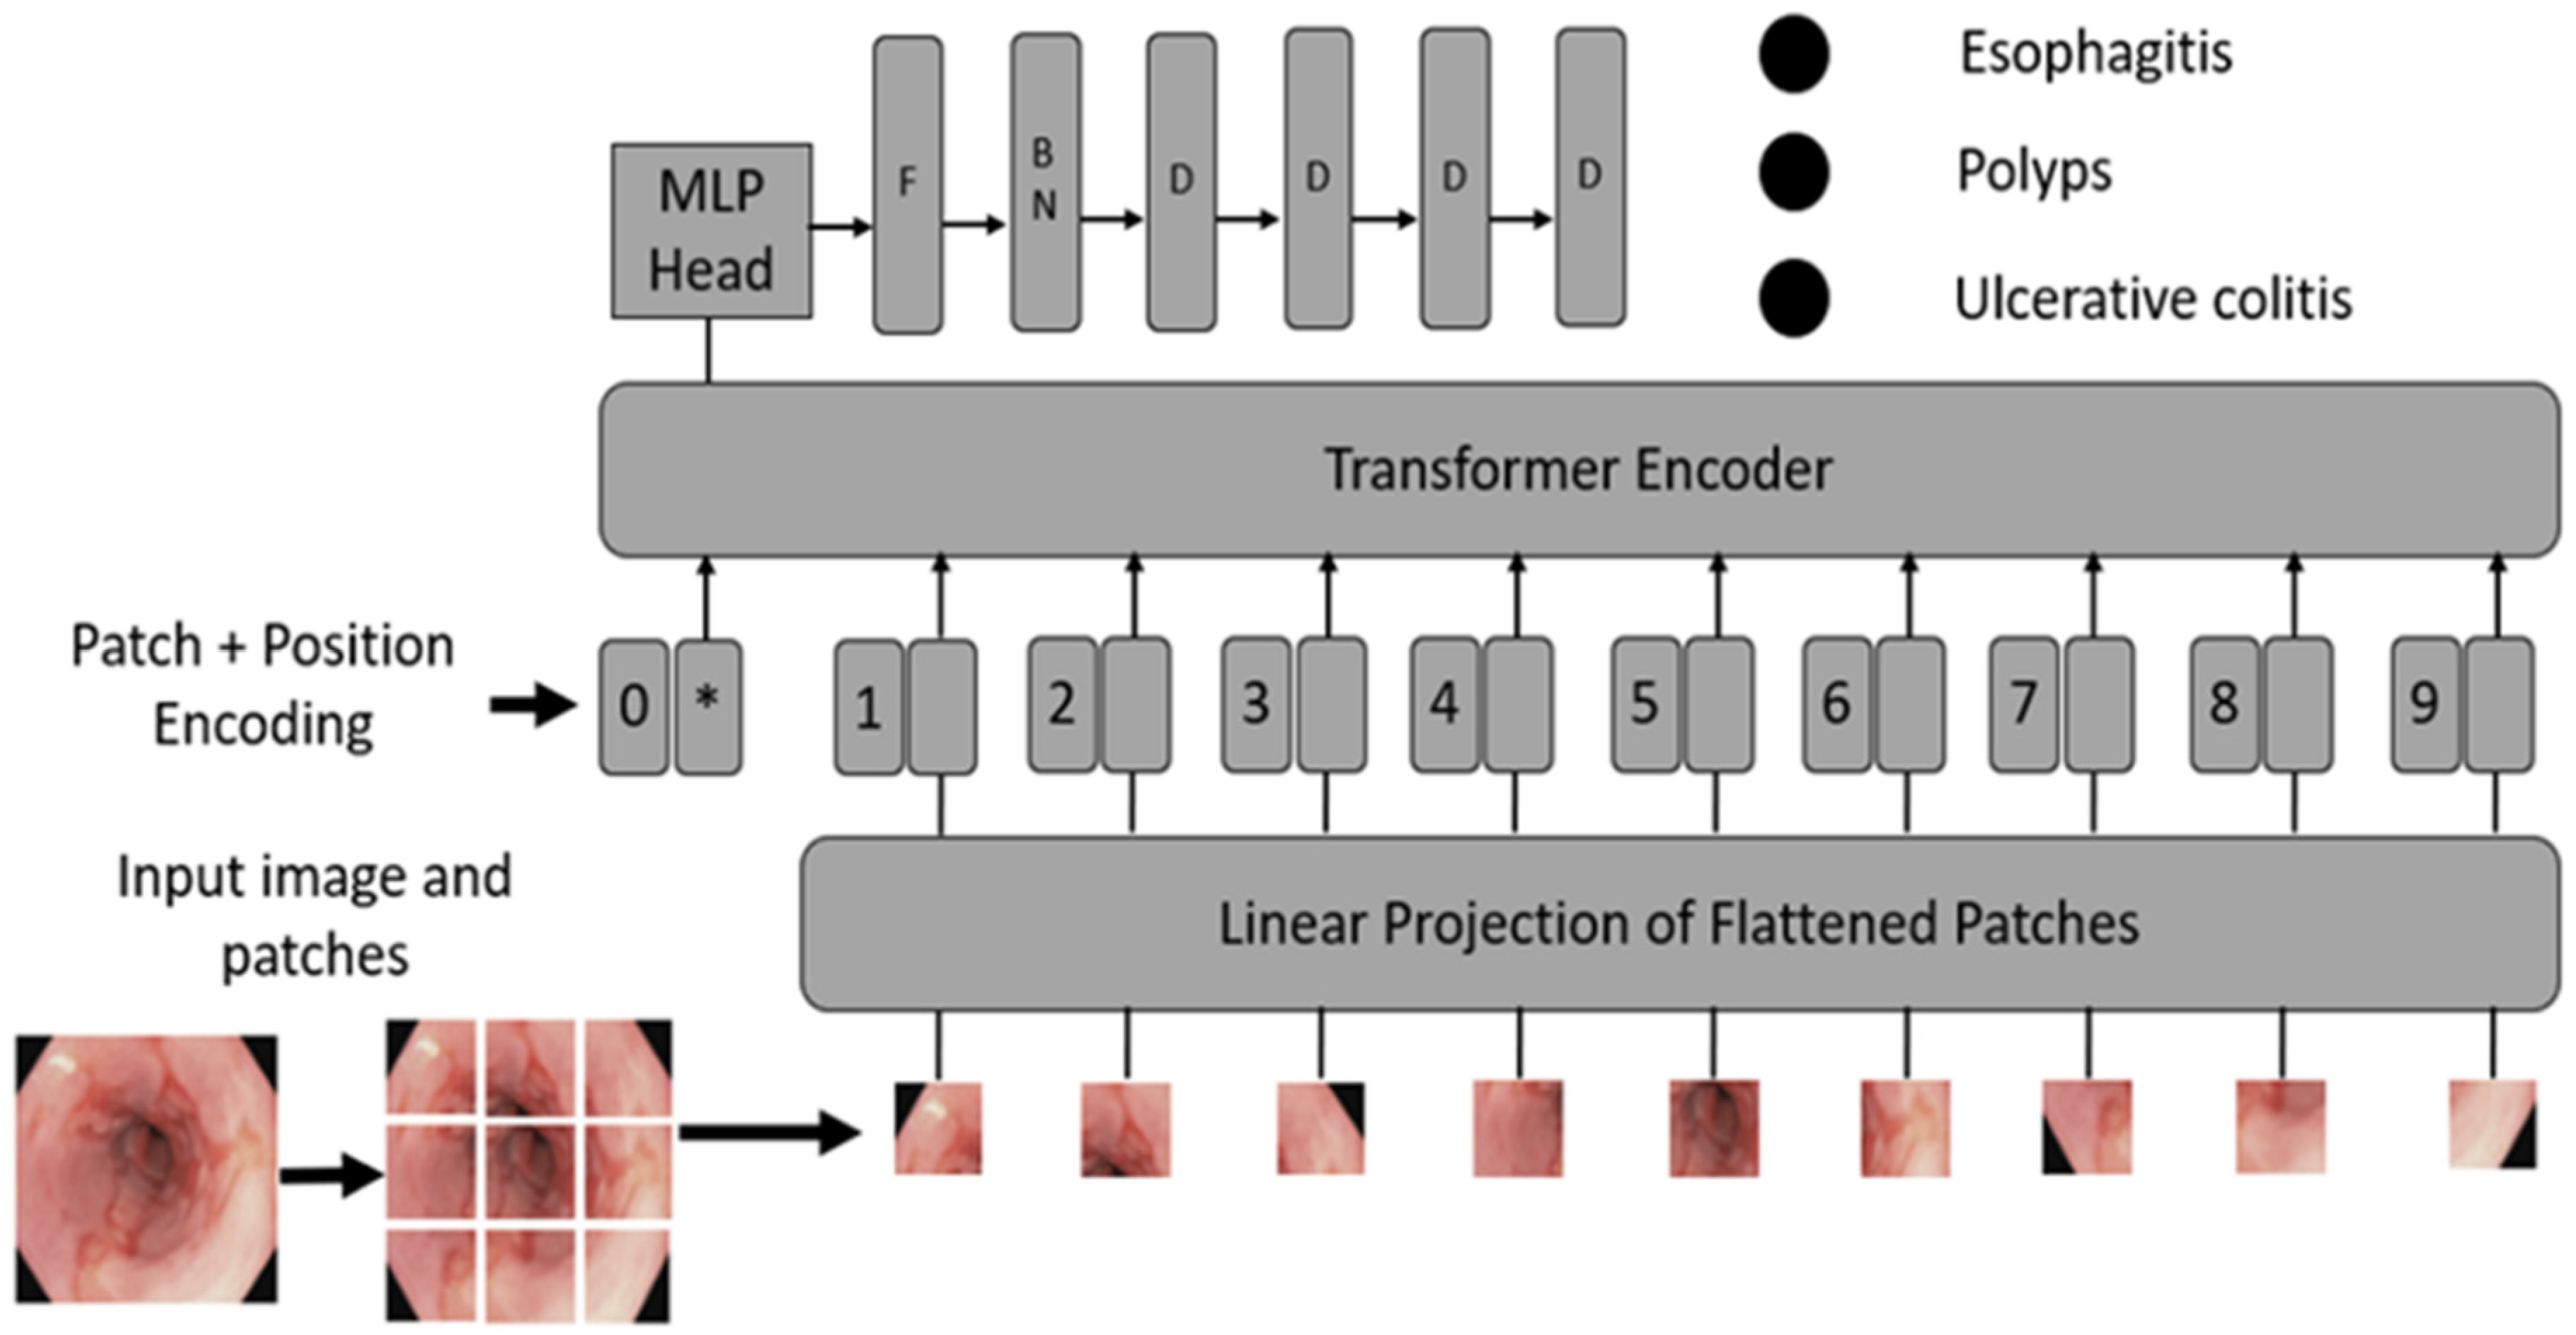

3.1.2. ViTCol Architecture

- Convert images into patches: Image patches are used as tokens of words by vision transformers, as in the original paper by Vaswani et al. [52]. For images, it is possible to take pixels; however, if pixels are considered, the computational cost will be high, and it is challenging to find hardware to process high-resolution images, as in the case of medical images. Thus, converting input images into patches has been proposed by Dosovitskiy et al. [36], as shown in Figure 2A. An image with is converted into patches of size .

- Learnable and positional embeddings: Patch projection is concatenated together with learnable embeddings, which are used later for classification. Transformers use positional embeddings to construct a certain order in the patches since, unlike time sequence models, patches do not spontaneously form into sequences. Similar to patch embedding, the positional encoding matrix is produced at random.

- Multilayer perceptron (MLP) head: The MLP head receives the transformer encoder unit’s outputs for classification. Despite the multiple outputs of the transformer encoder, the MLP takes only one output related to the class embedding, while the other outputs are ignored. The probability distribution of the labels that the associated images belong to is output by MLP. Figure 3 shows the ViT architecture used in ViTCol.